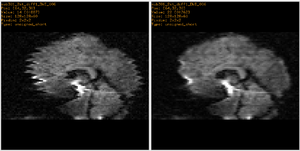

Example 1: Fixing Artifacts in DWI

The DWI data consists of 13 volumes -- a b0 and 12 gradient directions. This process was conducted 3 times per patient for a total of 39 volumes. The image below shows a particular slice in all 12 gradient directions and all 3 scans where the artifacts can clearly be seen in some of the gradient directions.

The problem can be alleviated by 2D registration between slices of a corrupted volume with the corresponding slice from the b0 volume, in which we assume the artifact is not present.

The problem can be alleviated by 3D registration between a corrupted volume with and the b0 volume, in which we assume the artifact is not present.